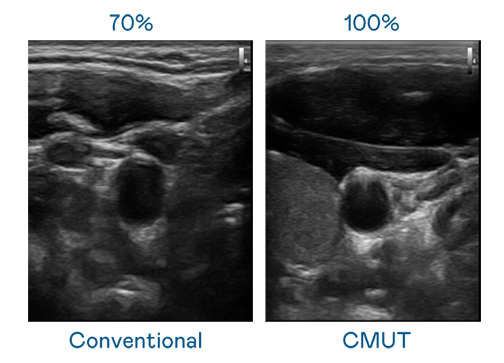

CMUT 技术是一种用电容式微机电元件来产生超音波讯号的技术。与传统 PZT 压电式技术相比,CMUT 频宽增加 30%,更宽频的超音波讯号让影像解析度大幅提升,是实现高影像品质医疗超音波扫描、促进精准医疗发展的关键技术。

超音波影像的解析度高低,首先取决于探头能发出的讯号频宽。凯发天生一触即发 CMUT 可提供高清晰的超音波讯号,提供高频宽、高灵敏度、影像纹理细节更高的超音波影像,协助医护人员缩短影像判读时间及利用精准的医疗影像进行诊断。